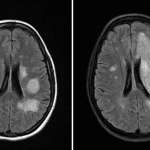

Indication: Multiple sclerosis, recent diagnosis of PML

- Markedly increased extent of T2/FLAIR signal hyperintensity throughout the left frontal and parietal lobes extending into the posterior limb of the left internal capsule and ventrolateral left thalamus

- No associated enhancement or restricted diffusion (though diffusion images are degraded by artifact)

- Mild associated mass effect without midline shift, herniation, or hydrocephalus

- Additional T2/FLAIR hyperintense lesions involving the bilateral cerebral hemispheres, pons, and middle cerebellar peduncles are similar in appearance

- No evidence of acute infarct or hemorrhage

- Immune reconstitution inflammatory syndrome (IRIS)

Markedly increased extent of T2/FLAIR signal hyperintensity without enhancement throughout the left frontal and parietal lobes extending into the posterior limb of the left internal capsule and ventrolateral left thalamus, which given abruptness of change most likely represents immune reconstitution inflammatory syndrome (IRIS) in this patient on treatment for multiple sclerosis.

Additional T2/FLAIR hyperintense lesions involving the bilateral cerebral hemispheres, pons, and middle cerebellar peduncles are similar in appearance, consistent with chronic demyelinating lesions.

Mild associated mass effect without midline shift, herniation, or hydrocephalus. No evidence of acute infarct or hemorrhage.